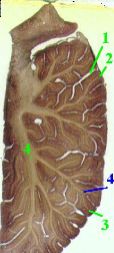

| Серое вещество | а) Серое вещество в мозжечке, как уже не раз упоминалось, представлено,

во-первых, корой (3), покрывающей всю поверхность извилин (2),

и, во-вторых, парными подкорковыми ядрами – зубчатым и рядом других.

б) При этом основная масса серого вещества приходится на кору.

| Белое вещество | а) Белое вещество (4) в извилинах имеет вид узких прослоек, которые переходят в более обширные “ветви” и “стволы” в срединной части мозжечка.

б) Это придаёт мозжечку характерный вид, обозначаемый как "древо жизни".